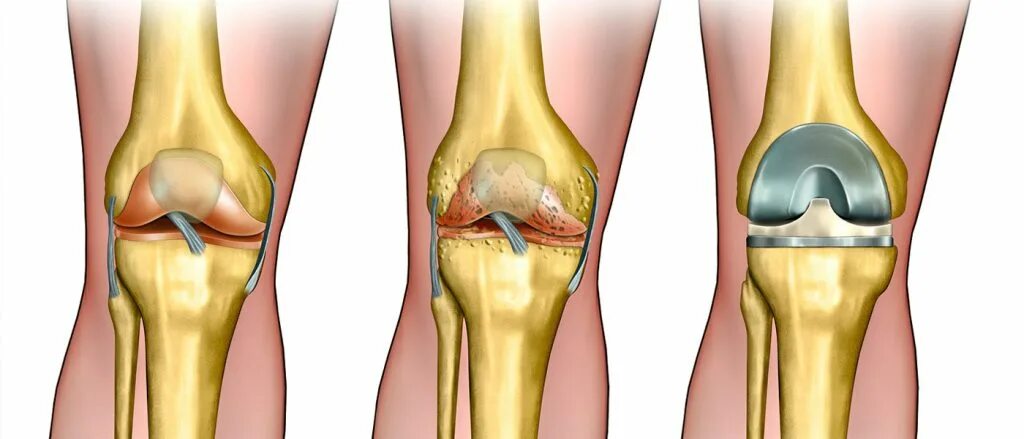

Как делают замену коленного сустава